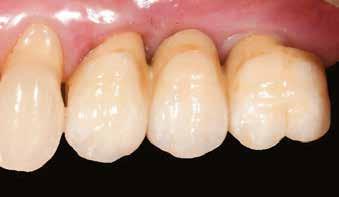

Prof. Curd Bollen, prof. Martin Jörgens (Hollandia)

EGY- ÉS KÉTRÉSZES KERÁMIA-

IMPLANTÁTUMOK A FOGÁSZATBAN

A kerámiaimplantátumok manapság már nem csupán divatos alternatívák, épp ellenkezőleg, a napi gyakorlatban hasznos kiegészítői az implantációs palettának. Esztétikai tulajdonságaik mellett a teljes fémmentesség is egy fontos előnyük, főleg olyan páciensek esetében, akiknél igazolt az allergia a titánnak azon ötvözeteire (5. osztály), amelyek tartalmaznak vanádiumot és alumíniumot, mivel ezek allergizáló hatása igen erős.

Ezenfelül tovább erősíti a használatuk melletti érveket, miszerint a kerámiaimplantátumok körül ritkábban tapasztalható periimplantitis.

Korábban a cirkonimplantátumok egyrészes (egyfázisú) kialakításban voltak csak elérhetők. Ma már azonban léteznek kétrészesek (kétfázisú, ún. hibrid-koncepció) is, amelyeket széles körben használnak a hiányzó fogak pótlására.

Cikkünk az egy- és kétrészes kerámiaimplantátumok előnyeit és hátrányait klinikai, tudományos, valamint páciensközpontú szempontok alapján hasonlítja össze.

Végezetül említünk néhány, általános ajánlást a kerámiaimplantátumok mindennapi használatával kapcsolatban.

1. ábra: Egy- és kétrészes kerámia- (cirkónium-dioxid) implantátumok (Z-Systems: Z5m & Z5-BL).

Az egy- és kétrészes implantátumok közti választás lehetősége már egy újabb jelenség. A kerámiaimplantátumok hajnalán csupán egyrészes, monoblokk rendszerek léteztek, a fej és az implantátum egy egységet képeztek 9 (1. ábra).

Az implantológiában mára az egyrészes és kétrészes implantátumokkal hasonló prognózist lehet elérni. A legfrissebb kutatások egyértelműen azt mutatják, hogy kiváló klinikai eredmények érhetők el az egy- és kétrészes kerámiaimplantátumokkal is. Viszont a kétrészes kerámiaimplantátumok esetében még nem áll rendelkezésre elegendő hosszú távú tudományos adat, amely alátámasztaná mindennapi használatukat. Ezért kiemelten fontos, hogy ilyen implantátumok beültetése előtt a pácienst teljeskörűen tájékoztassuk, és ezt követően egyezzen csak bele a kezelésbe.